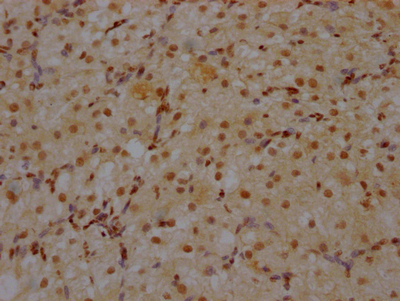

IHC image of CSB-RA930964A0HU diluted at 1:100 and staining in paraffin-embedded human ovarian tissue performed on a Leica BondTM system. After dewaxing and hydration, antigen retrieval was mediated by high pressure in a citrate buffer (pH 6.0). Section was blocked with 10% normal goat serum 30min at RT. Then primary antibody (1% BSA) was incubated at 4℃ overnight. The primary is detected by a Goat anti-rabbit IgG polymer labeled by HRP and visualized using 0.05% DAB.

IHC image of CSB-RA930964A0HU diluted at 1:100 and staining in paraffin-embedded human brain tissue performed on a Leica BondTM system. After dewaxing and hydration, antigen retrieval was mediated by high pressure in a citrate buffer (pH 6.0). Section was blocked with 10% normal goat serum 30min at RT. Then primary antibody (1% BSA) was incubated at 4℃ overnight. The primary is detected by a Goat anti-rabbit IgG polymer labeled by HRP and visualized using 0.05% DAB.